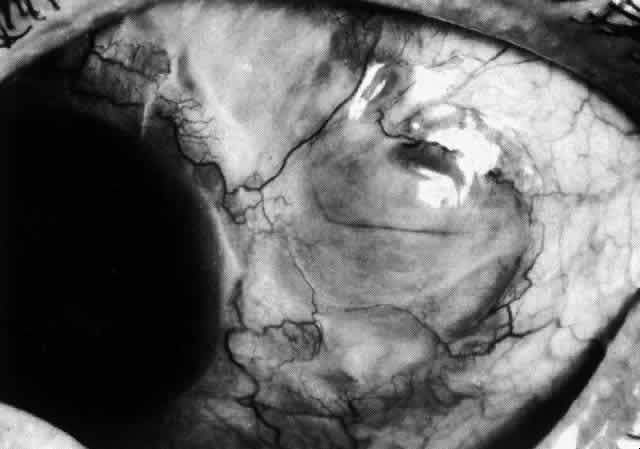

scleritis. Posterior Scleritis Because the posterior sclera is invisible, the diagnosis of posterior scleritis

is made only if the anterior sclera is also involved or some

other sign or symptom leads one to suspect it. Posterior scleritis is

much more common than previously suspected, as recent clinical and pathologic

studies have shown.19,28,29 There are two distinct forms of posterior scleritis. The first is usually

associated with an anterior scleritis. This granulomatous disorder, like

its anterior counterpart, can be diffuse, nodular, or necrotizing

in character and is associated with the connective tissue diseases. The

second form occurs in young patients of all races who are 9 to 40 years

of age. It is always diffuse in character but is not associated

with any systemic disorder. Both forms may cause uveitis if the inflammation

affects the ciliary body, and in both forms the patient may develop

exudative retinal detachments, choroidal folds, and swelling of

the disc (Figs. 51 and 52). The granulomatous type may also involve the structures outside the globe, causing

proptosis (Fig. 53), limitation of ocular muscle movement, and, uniquely, retraction of the

lower lid on attempted elevation of the eye (Fig. 54). Diagnosis is with B-scan ultrasonography.  Fig. 51. Swelling of the optic nerve head and hemorrhage near the disc in a patient

Fig. 52. Fundus appearance after resolution of exudative detachment in patient with

severe posterior scleritis. Macula was affected and vision much impaired. (Watson PG: Management of scleritis. In: Recent Advances in Ophthalmology, Vol 5. London, Churchill-Livingstone, 1975) Fig. 52. Fundus appearance after resolution of exudative detachment in patient with

severe posterior scleritis. Macula was affected and vision much impaired. (Watson PG: Management of scleritis. In: Recent Advances in Ophthalmology, Vol 5. London, Churchill-Livingstone, 1975)

|